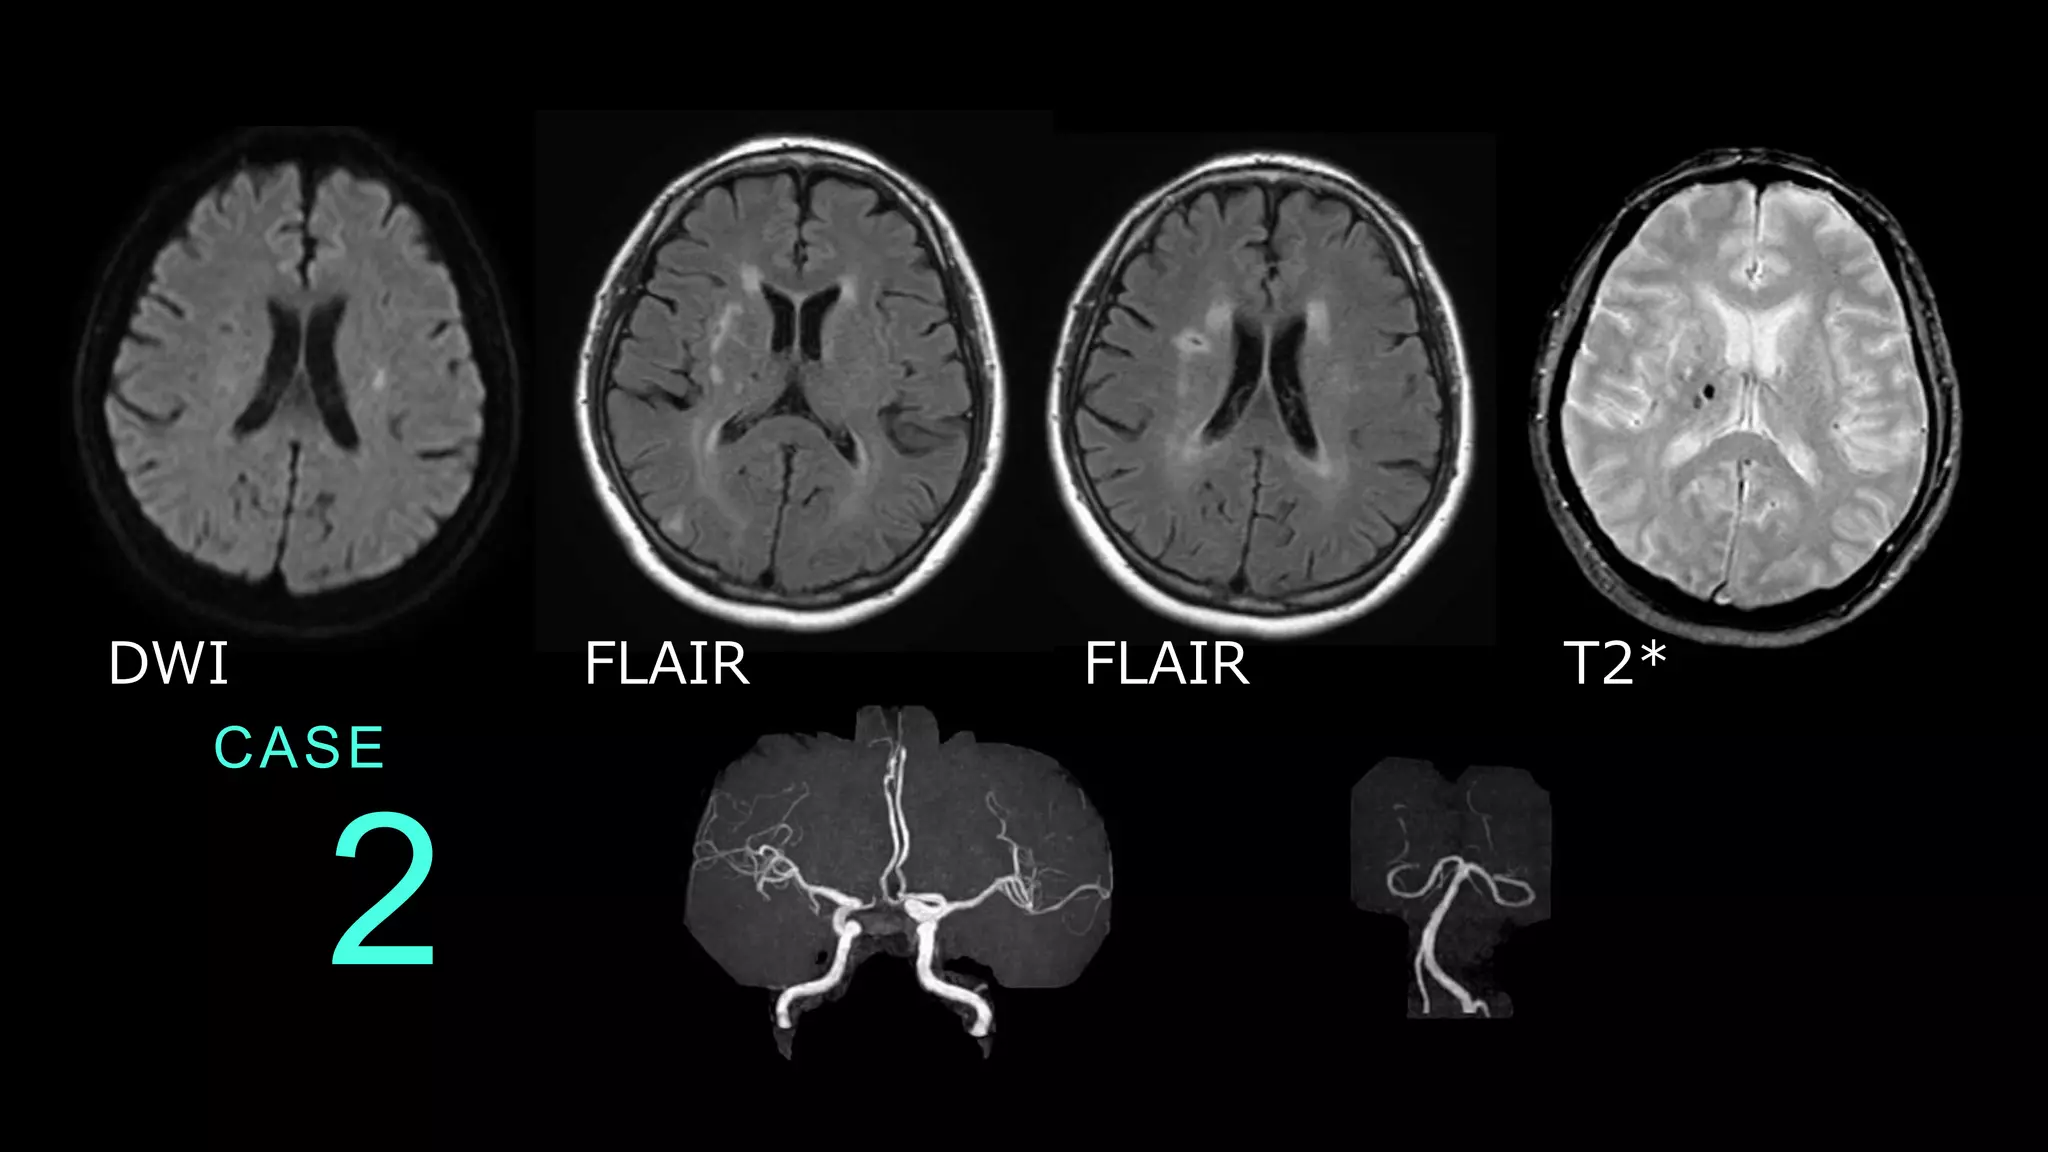

2 CASE DWI FLAIR FLAIR

2 CASE DWIで放線冠レベルのスライスで 淡い高信号の白質病変を認める。 DWI

CASE 2 DWIで指摘された病変はFLAIRでは目立たない。 FLAIRでは、脳室周囲の白質に高信号病変が散在し ている。 FLAIR FLAIR

2 CASE T2*では、右側大脳の基底核レベルのスライスに、 microbleedsが指摘できる。 T2*

CASE 2 MRAでは、前方循環・後方循環ともに全体的 な口径不整や血管蛇行が目立つ。

2 CASE コメント: FLAIRでは脳室周囲の白質に高 信号病変を認め、陳旧性虚血性 変化があります。T2*では出血 痕があり、MRAでも動脈硬化性 変化が指摘できます。総じては 血管障害リスクが高い、と読み 取れます。 症例はDWIで指摘される、ラク ナ梗塞。